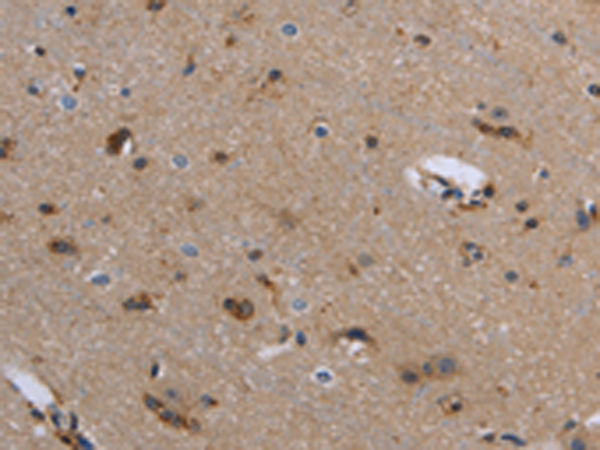

分类: 科研抗体货号: P01395别名: GK1; GALK; HEL-S-19应用: WB,IHC反应种属: Human, Mouse